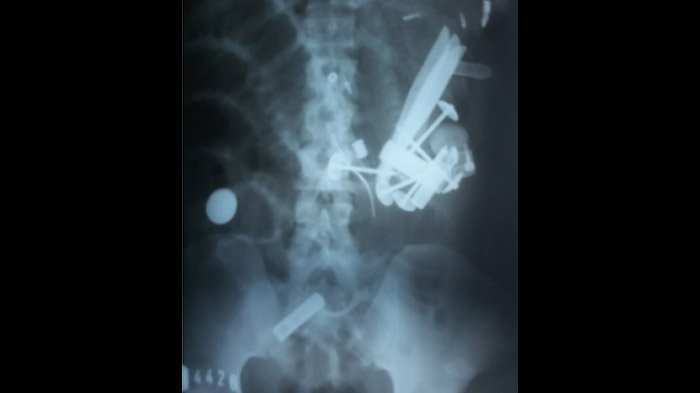

Hasil rontgen yang menunjukkan banyak logam di tubuh (ilustrasi)

TRIBUNMANADO.CO.ID, MANADO - Para ahli bedah mengeluarkan lebih dari 100 logam berbagai bentuk dan ukuran dari dalam lambung seorang pria di Prancis. Demikian menurut laporan kasus dalam sebuah jurnal ilmiah baru-baru ini.

Benda-benda yang ditelannya termasuk paku, pisau, sekrup, mur, koin, dan sendok, demikian menurut laporan kasus dalam jurnal BMJ Case Reports terbitan 27 September, seperti dikutip dari Live Science pada Senin (9/10).

Pria itu sangat sering menelan benda-benda logam dalam rentang waktu cukup lama sehingga benda-benda itu menggumpal dalam lambungnya, menjadi gumpalan yang diistilahkan sebagai "bezoar."

Gumpalan bezoar itu menjadi semakin besar hingga menyumbat pylorus, yaitu saluran yang menghubungkan lambung dan usus kecil. Akibatnya, menurut laporan kasus, lambungnya tidak bisa dikosongkan.